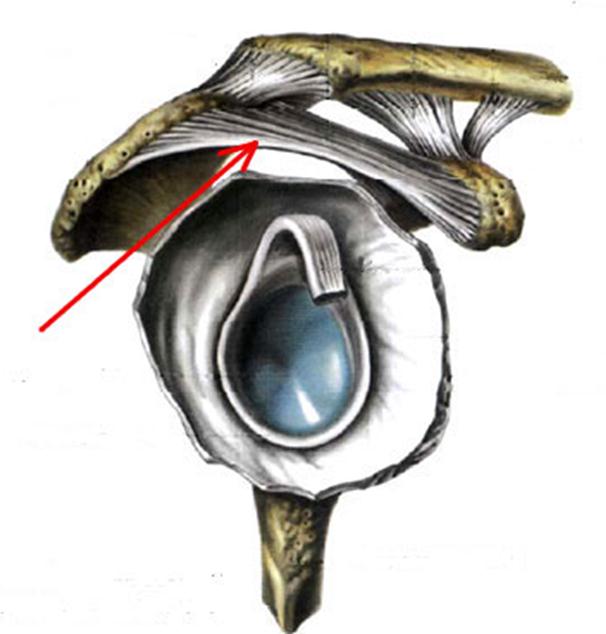

Стрелка указывает на lig....

-:acromioclaviculare

-:coracoacromiale

+:trapezoideum

-:conoideum

-:transversum scapulae superius